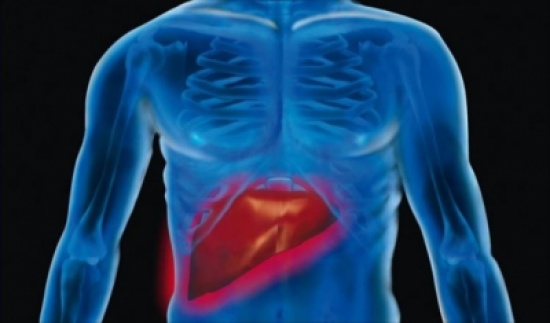

الحل الوحيد للتغلب على سرطان الكبد.. تعرفوا عليه!

المدينة نيوز:- يسبب سرطان الكبد الوفاة أكثر من أنواع اخرى من السرطان، بحسب الطبيب الاختصاصي في الاورام وأمراض الدم د.فادي نصر، خصوصاً أنه غالباً ما يتم التشخيص في مراحل متقدمة منه.

من هنا أهمية الخضوع لاختبار سرطان الكبد بهدف تشخيصه في مرحلة مبكرة وتحسين فرص العلاج، في ما يتعلّق بالأشخاص الذين لهم تاريخ عائلي من الإصابة به والذين هم عرضة للإصابة ببعض أنواع التهاب الكبد والذين يعانون سمنة مفرطة. هذا مع الإشارة إلى أن سرطان الكبد يعتبر السبب الثاني للوفاة من السرطان على مستوى العالم حيث يسبب وفاة 746 ألف شخص سنوياً. ايضاً في أوروبا يعيش أقل من 10 في المئة من المرضى لأكثر من 5 سنوات بعد التشخيص.

استناداً إلى ذلك، دعت شركة "باير" إلى الكشف المبكر عن سرطان الكبد لإنقاذ الحياة بتسليط الضوء على هذا المرض الذي يصيب نسبة 4 في المئة من مرضى السرطان في لبنان، ومن المتوقع أن ترتفع هذه النسبة إلى 6 في المئة لدى النساء و8 في المئة لدى الرجال بحلول عام 2018.

تجدر الإشارة إلى أنه يسبق التهاب الكبد الفيروسي "ب" المزمن تغيير خبيث في الخلايا لدى 8 أشخاص من 10 مصابين بسرطان الكبد. وينذر التهاب الكبد C بالسرطان تماماً كالتليّف الكبدي والتغيّر المرضي في نسيج الكبد.

ويعتبر التشخيص المبكر أساسياً لنجاح العلاج وضمان فاعليته لأنه يمكن التخلص من الورم في مراحل مبكرة من خلال الجراحة. لكن في كثير من الحالات يشخص المرض عندما يصبح الورم غير قابل للاستئصال بالجراحة، إذ لا تظهر الأعراض إلا بعد بلوغ المرض مرحلة متأخرة، وتشمل فقدان الشهية والغثيان والشعور بألم وضغط في أعلى البطن.